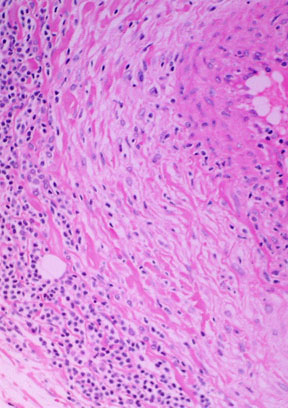

Blood vessels: